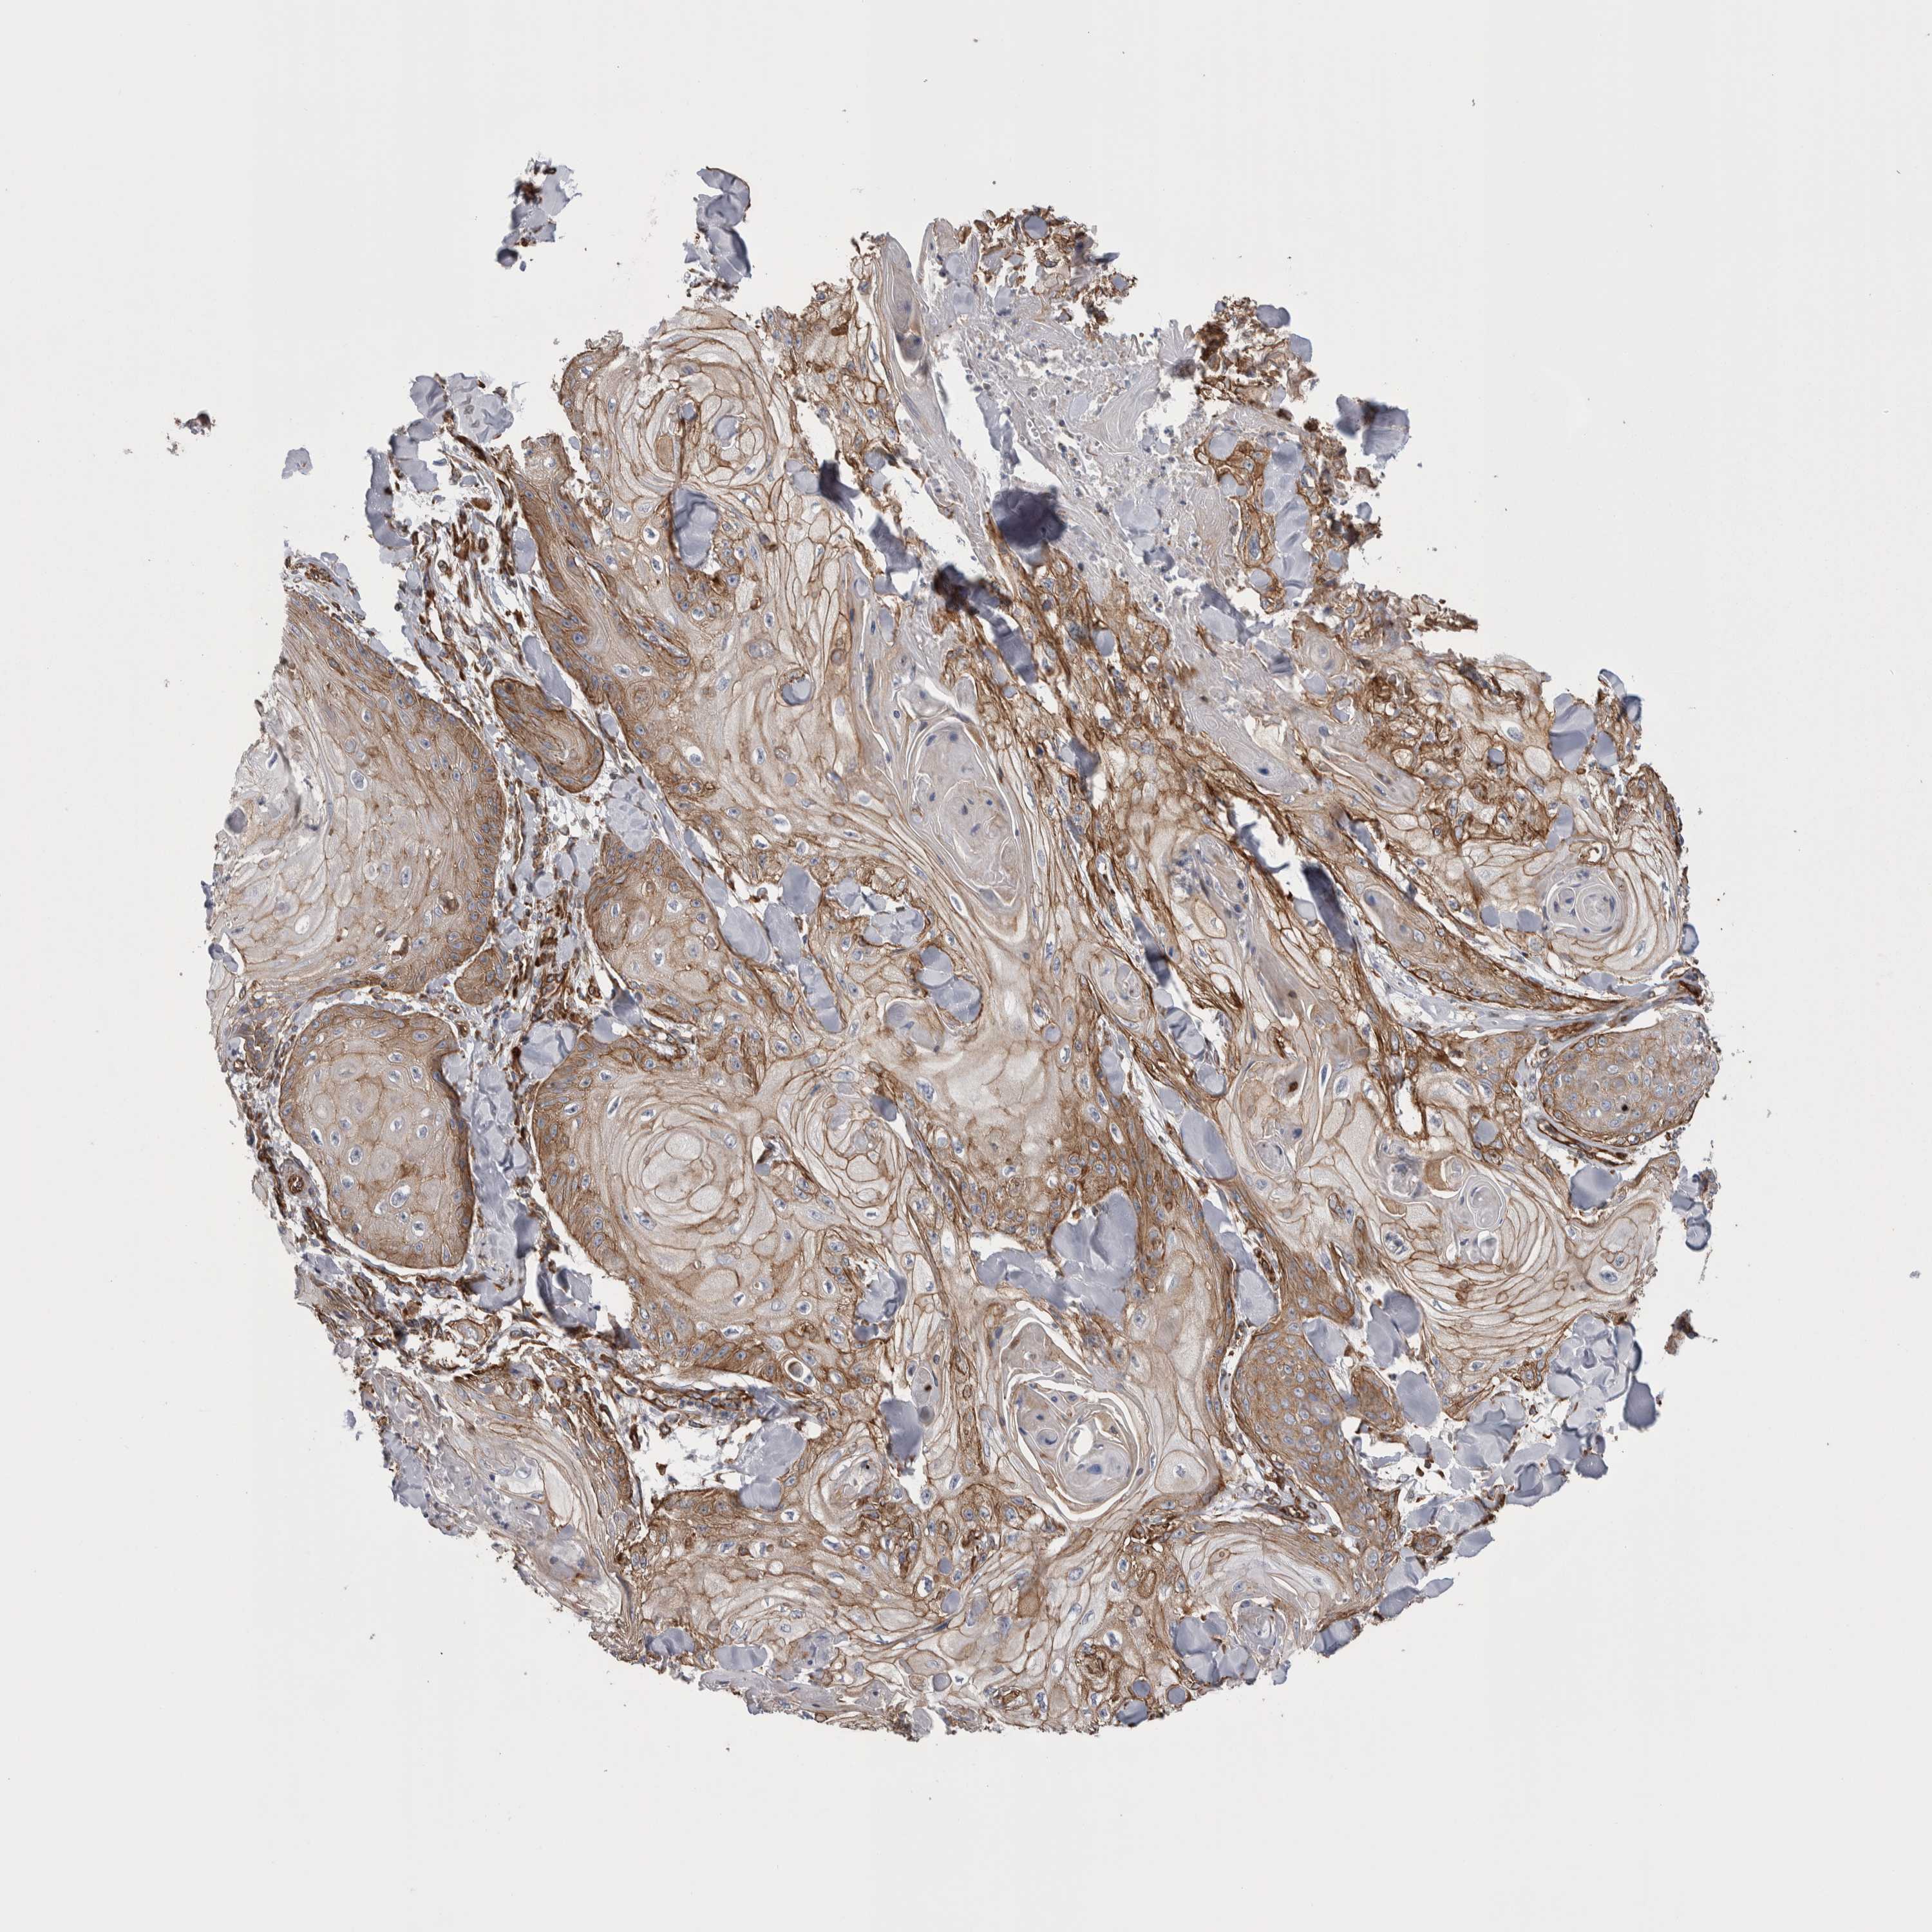

Basal cell and squamous cell cancer

SKIN CANCER - Protein expressioni

A mouse-over function shows sample information and annotation data. Click on an image to view it in a full screen mode. Samples can be filtered based on level of antibody staining by selecting one or several of the following categories: high, medium, low and not detected. The assay and annotation is described here.

Each image is clickable and will lead to virtual microscopy that enables deeper exploration of all samples and also displays staining intensity scores, fraction scores and subcellular localization as well as patient and tissue information for each sample.

Antibody HPA020192

Basal cell carcinoma